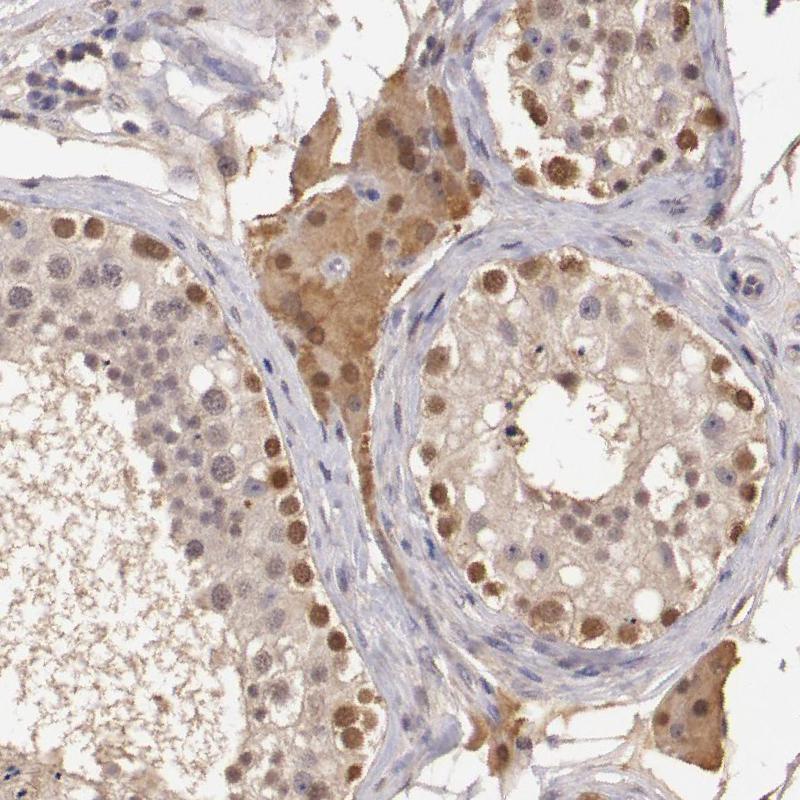

Immunohistochemistry analysis in human liver and pancreas tissues using HPA001401 antibody. Corresponding SOD1 RNA-seq data are presented for the same tissues.